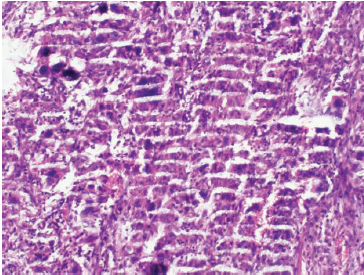

问:切片出现叠加褶皱怎么办?

答:此类情况主要分为两种,一种是切片时出现问题,譬如组织相对较硬,其中含有钙化组织,或者是切片时刀头不够锋利,从而导致褶皱的产生;蜡块未完全冷却时质地较软,切片时依旧容易出现褶皱。另一种情况是在漂片时水温不够,切下的组织切片在漂洗时无法完全展开,也会导致褶皱的形成。

解决方案刀头不够锋利需要重新更换刀片,漂片的水温一般需要需要比石蜡的熔点更低10℃,也需要调节漂片时间,可以让切片完整舒展。如果是组织中原先就会出现部分钙化等,则是难以避免。